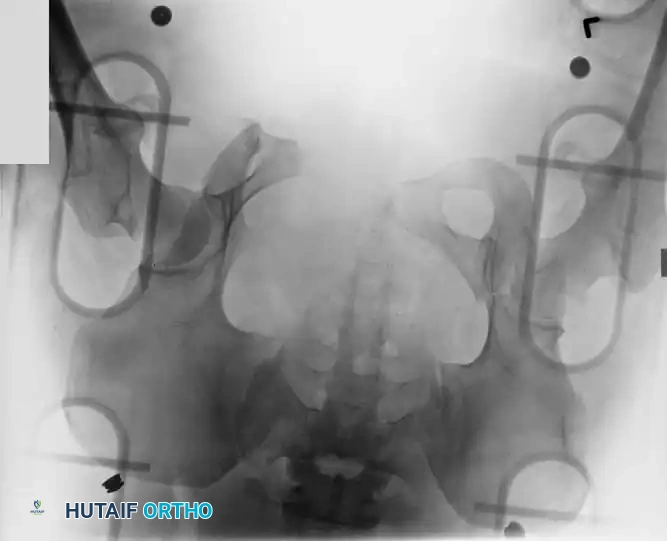

Radiographic Evaluation

Standard evaluation begins with an Anteroposterior (AP) pelvis radiograph. However, definitive surgical planning requires specialized views and advanced imaging.

• Inlet View: Directed 45 degrees caudad. Best evaluates anterior-posterior translation, internal/external rotation, and sacral impaction.

• Outlet View: Directed 45 degrees cephalad. Best evaluates vertical translation and sacral foraminal anatomy.

• CT Scan: The gold standard for evaluating posterior ring injuries, sacral dysmorphism, and preoperative planning for percutaneous fixation.

Image